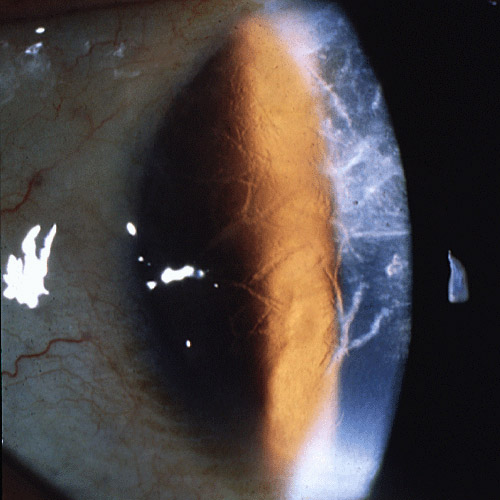

가장 전형적인 type 1 격자각막이상증은,

상염색체 우성으로 유전하여, 10세 이전에 발병하여,

양안의 각막 기질 표층부에 격자형의 가치진 모양의 선이 발생합니다.

그리고 소결정의 혼탁이 발생하면서, 점점 격자 형태가 갖추어집니다.

이러면서 이러한 각막 혼탁이 상피층 아래에 위치하기 때문에, 각막 상피의 진무름이 일직 발생합니다.

이후 40-50대에는 각막 혼탁으로 인한 심한 시력장애를 유발하게됩니다.

각막의 중심부를 주로 침범하며, 주변부는 침범하지 않는 것이 특징입니다.